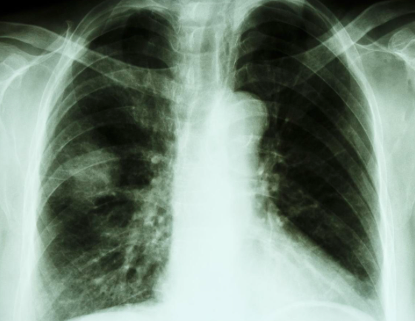

小方感觉不对劲 , 就赶紧向工头请了假 , 到了医院 , 医生建议他先做一个肺部CT , 做完发现肺部竟然出现了一个8mm大的结节 , 最终被确诊为肺结节 。